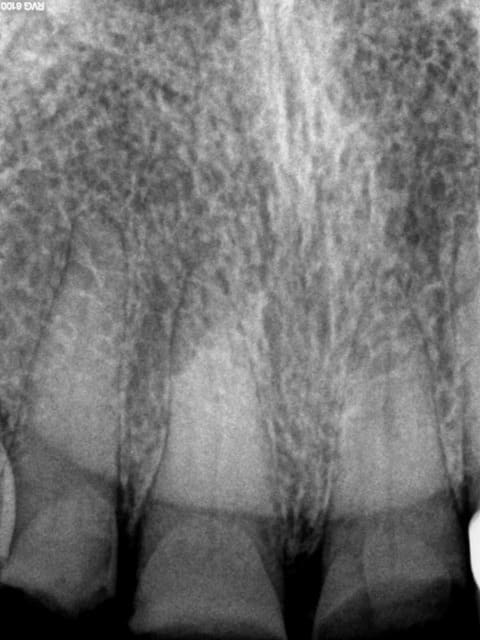

Et 2 autres pour terminer la journée. Ca fait 5 endos molaires aujourd'hui.

Pas trouvé de MV2 sur la 7.